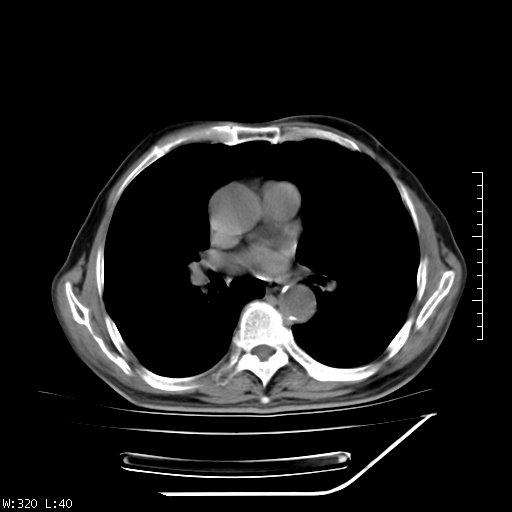

标题: CT23994:男、72、咳嗽、气短两月余,近来消瘦。 [打印本页]

标题: CT23994:男、72、咳嗽、气短两月余,近来消瘦。

右上肺实变,与胸膜关系密切,右肺容积缩小,隆突下淋巴结增大,考虑1 肺结核 2 肺癌

以下是引用muzi888在2010-1-6 9:43:00的发言:[br]右上肺实变,与胸膜关系密切,右肺容积缩小,隆突下淋巴结增大,考虑1 肺结核 2 肺癌